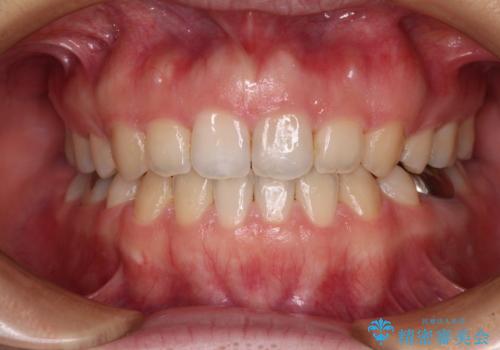

治療は順調に進み、予定された期間で終了することができました。

装置除去後には、スッキリとした口元となり、大変満足していただきました。